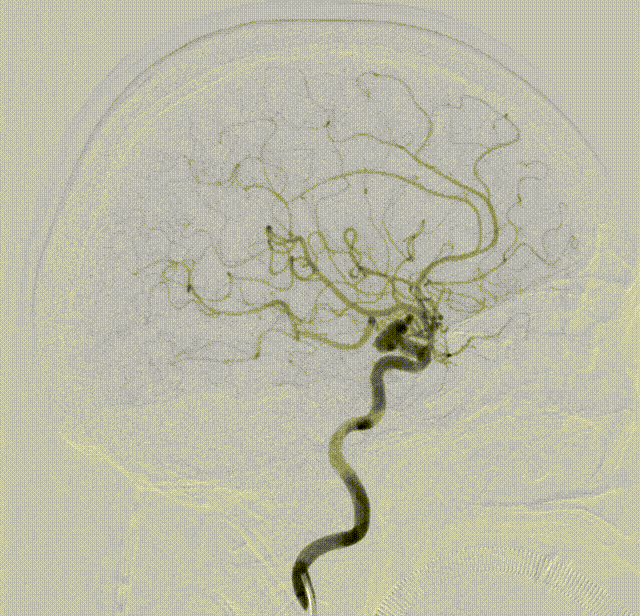

DSA可见右侧颈内动脉交通段动脉瘤,6.60*5.85mm,其上可见子囊,绝对宽颈,后交通动脉自瘤体发出,双侧胚胎型大脑后动脉,椎动脉造影双侧大脑后动脉可见显影,压颈可见后交通向前代偿良好。

术后工作位及正侧位造影见动脉瘤栓塞满意、载瘤动脉通畅

术后3D及重建可见动脉瘤及瘤颈不显影(Raymond I级),各分支血管通畅,支架打开满意